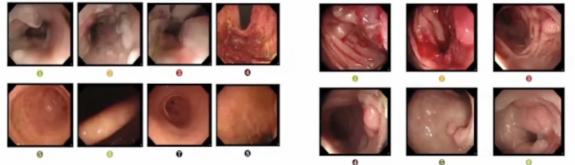

肠镜病理(图4):(升结肠粘膜活检3块)结肠粘膜组织,其中1块结肠粘膜呈高级别管状腺瘤(粘膜内癌),取材浅,刚果红染色阴性。

图4 升结肠粘膜活检病理综合上述结果,张霞大夫给患者下的入院诊断为: